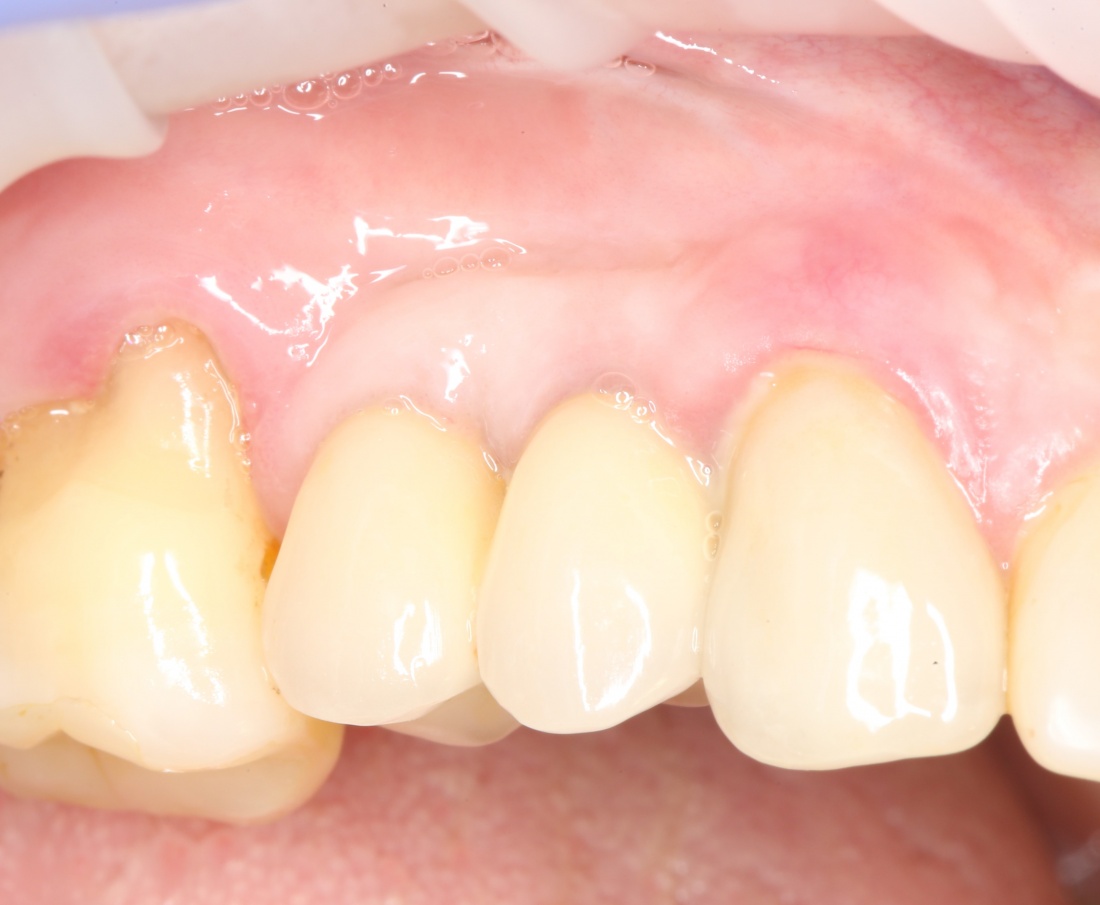

Как видите, я перенес разрез вестибулярно, примерно в проекции предполагаемого субантрального доступа. Таким образом, я получаю тот же обзор при меньшей по площади ране. Это безопаснее. Такой доступ очень просто и легко зашивается, рана заживает быстрее и с минимальным дискомфортом. Кроме того, слизистая оболочка вершины альвеолярного гребня, где мы будем потом делать следующий разрез для установки имплантов, осталась неповрежденной, мы не оставили на ней рубцов, которые могут осложнить заживление при повторном входе для установки имплантов.

Синуслифтинг одномоментно с установкой имплантов.